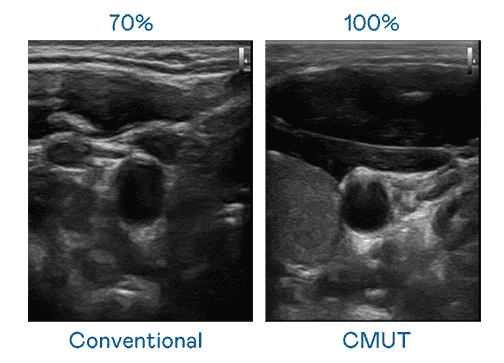

CMUT 技术是一种用电容式微机电元件来产生超音波讯号的技术。。与传统 PZT 压电式技术相比,,,,CMUT 频宽增加 30%,,,更宽频的超音波讯号让影像解析度大幅提升,,是实现高影像品质医疗超音波扫描、、、促进精准医疗发展的关键技术。。。

大频宽带来超清晰影像

超音波影像的解析度高低,,,首先取决于探头能发出的讯号频宽。。Wepay CMUT 可提供高清晰的超音波讯号,,,提供高频宽、、高灵敏度、、、、影像纹理细节更高的超音波影像,,,协助医护人员缩短影像判读时间及利用精准的医疗影像进行诊断。。。